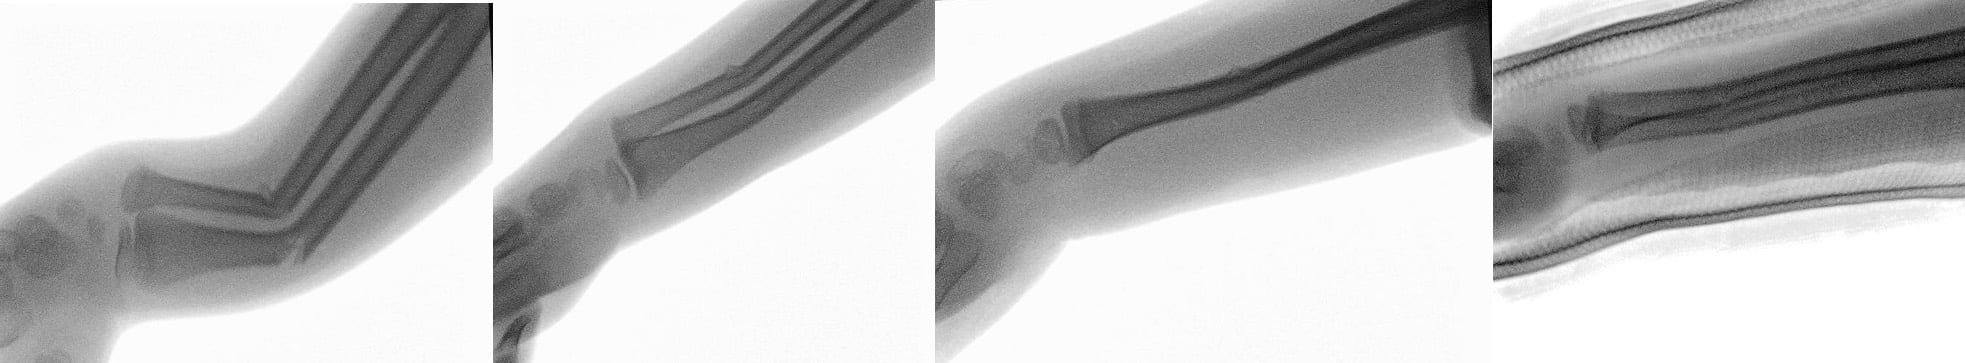

Fluoroscopy provides real-time visualization of a reduction, theoretically improving anatomical alignment. The evidence for this benefit is mixed, however, and it has not been well-studied in the emergency department. Two adult studies and one pediatric study comparing reductions with and without fluoroscopy guidance demonstrated no significant difference in reduction quality or need for surgery.4,5,6 Conversely, a retrospective cohort study of 279 wrist and forearm fractures found a significant improvement in reduction quality (measured by degrees of angulation) and need for surgery.3 Ultimately, these studies involved reductions performed by orthopedic surgeons, and there is potential that the visual cue from fluoroscopy could provide greater benefit to ED physicians who have less reduction experience. The images below provide an example of using fluoroscopy over the course of a reduction to improve anatomical alignment, including during splint application.

After fluoroscopic-guided reduction under procedural sedation, the patient’s radius/ulna fracture was reduced to anatomical position with minimal angulation, and he was able to avoid surgery. When applied to the appropriate orthopedic injury, fluoroscopy can help achieve better reduction quality, maintain the reduction, and provide time savings in the ED.